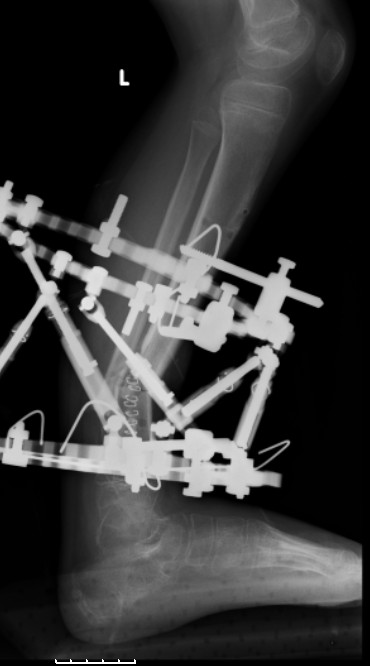

Another choice is simply perform shortening + posterior angulation with Ilizarov or TSF , than gradual correction of the angulation.After all apply third ring on the proximal tibia and start lengthening.

We had recently similar case in 14 years old boy with 45 mm bone defect after open tibial fracture.Boy doing excellent .This technique is not new, Sasha Lerner did it in Rambam , Rozbruch wrote also.

Another advantage of this techniqe is relaxation of soft tissue and possibility for closure even large defects of the skin.In your case I will apply ring on the foot and mid diaphysis of the tibia ,removal of the fibular plate,sindesmotic wire, and after correction of angulation on the proximal tibia.

Действительно, если есть длинная косая линия на проксимальном отломке, это жалко будет не использовать. Можно сделать коррекцию угла не обратным разведением фрагментов, а оставить их в контакте, и сделать кортикотомию проксимальнее на 2-3 см. Можно и сейчас отсечь такой фрагмент и транспортировать его с разворотом. Наверно, вариант с ангуляцией более технологичен.

Да, надо удалить все железо, сделать для ангуляции остеотомию малоберцовой на уровне дефеормации, а после восстановления оси сразу освободить стопу. То есть в дистальном отломке tibia надо побольше

спиц с упорами, а на диафизе только half-pins с передне-внутренней стороны, чтобы как можно меньше пострадала передняя группа мышц.

Sasha kuda delsya Lateral final snimok??

Sasha kuda delsya Lateral final snimok?